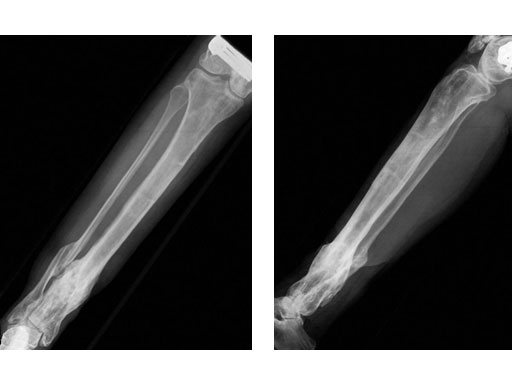

A 33-year-old female sustained a grade III open fracture of the right lower leg.

Case provided by Michael Raschke, Mnster, DE